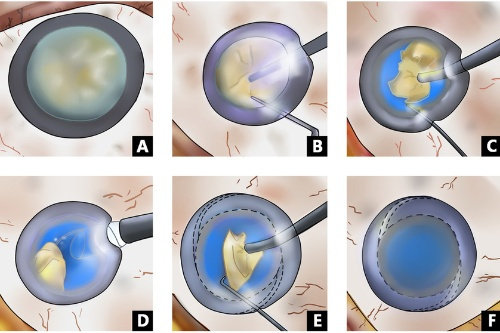

人工晶体植入术(ICL)通过在眼内植入一个特殊的人工晶体来矫正视力,这种手术避免了切削角膜的风险,且对角膜厚度没有严格要求。对于近视度数高达1500度的患者来说,这种手术方式可能更为适合。ICL手术适应的近视度数范围广泛,通常可矫正300度到2300度的近视,以及600度以下的散光。